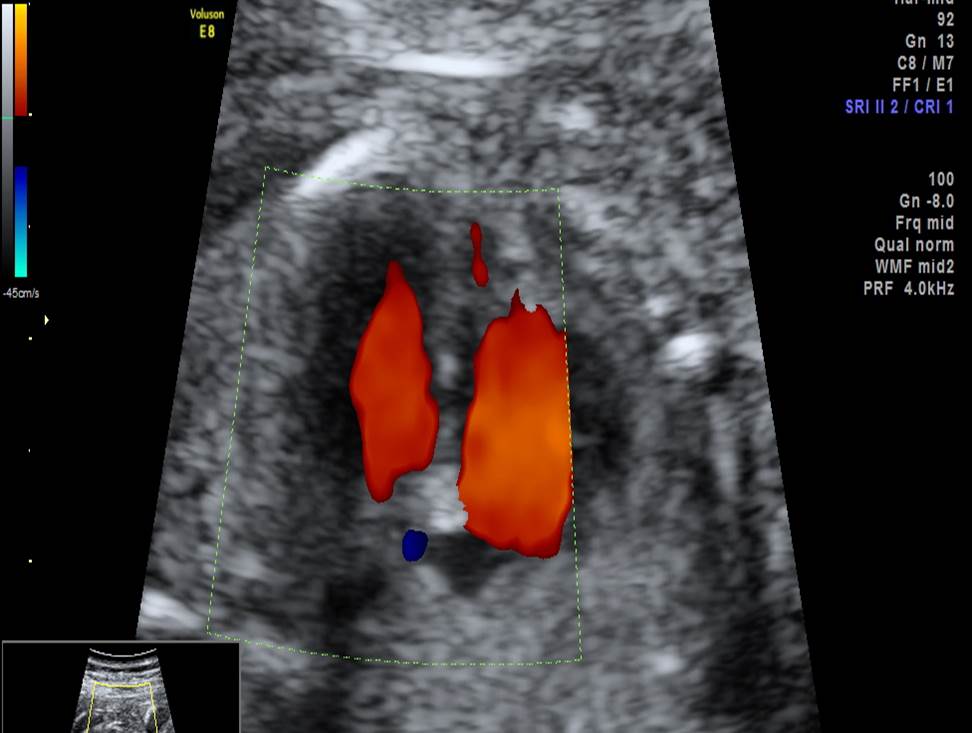

Вопрос 4

- Проанализируйте изображения плода в 20 недель, есть ли у него какие-либо маркеры хромосомной патологии?

- Необходимо ли рекомендовать инвазивную диагностику? Пациентке 25 лет, в 1 триместре не обследовалась